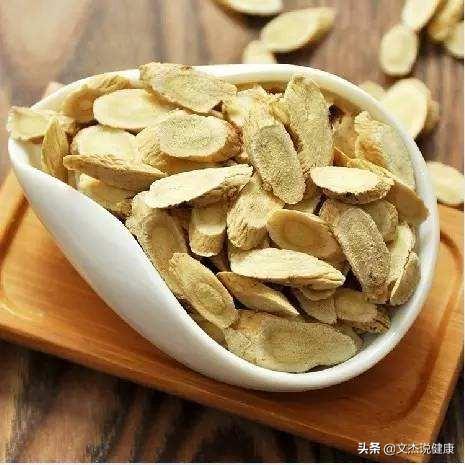

ハトムギ:

現在、人々の健康管理に対する意識がますます強くなるにつれ、ハトムギなどのハーブはより多くの人々に知られ、歓迎されるようになり、また、飲料水として、料理作りの材料として、そして気を補う健康補助食品として、常用されている。ハトムギは温性で味が甘く、主に漢方薬として免疫調整、老化防止、利尿、降圧、肝保護などの目的で使用される。その強壮作用は主に脾気虚に効く。いわゆる脾気虚とは、主に咳が出る、いつも痰を感じているが咳き込めない、息切れがする、少し動いただけで息苦しくなる、眠気がする、全身がだるい、全身の元気がない、食欲に影響がないなどの症状があり、これらは脾気虚の基本的な現れです。以上のような特徴を満たす場合、ハトムギは気を補うために応用できる。

アストラガルスまたはアストラガルス・モングホリカス

1, ハトムギ

ハトムギは、中国の伝統的な漢方薬として、また日常生活で非常に一般的であり、それは一種の貴重なハーブに属していない、普通の人々が頻繁に使用することができます。

ハトムギの効能については、私たちが最もよく知っているのは、ハトムギの強壮効果かもしれない。特に、体が弱っているときや重い病気から回復したときには、ハトムギを使って気を補い、不足した気を補うことが多い。漢方薬辞典』によると、ハトムギは温性で甘味があり、気と固形表面、毒素と膿、利尿、筋肉の成長を補う働きがある。主な治療法は、気虚の虚弱体質、長引く下痢や脱肛、発汗、水腫、子宮脱、慢性腎炎蛋白尿、糖尿病、ただれが長期間治らないなどである。